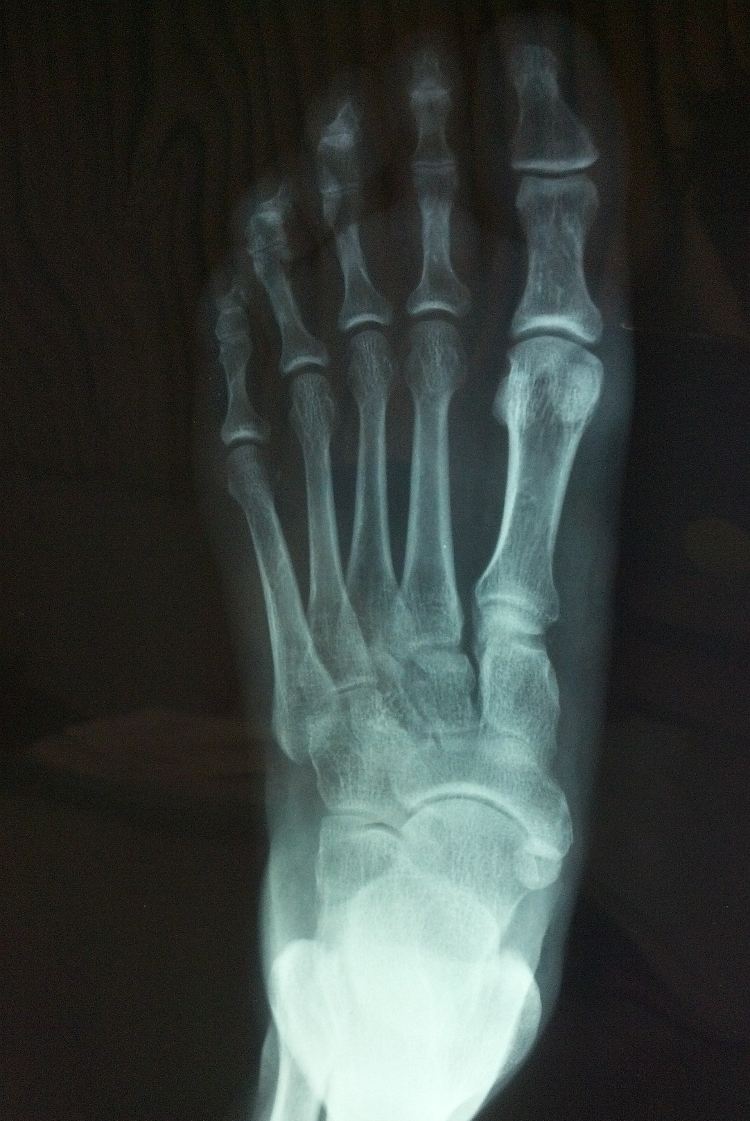

The plantar or Plantar Fascia is a band of connective tissue that is found under the feet. It joins the heel with the ball of the feet and acts as a natural shock absorber and suspension when running, walking, and jumping.

Doctors and scientists had presumed for a long time that the disorder was an inflammation of the Plantar. However, it was discovered not too long ago that the inflammation is actually a symptom of the cause itself. In reality, plantar fasciitis is a breakdown of the tissue through microtrauma.

X-Ray Of Foot Plantar Fascia